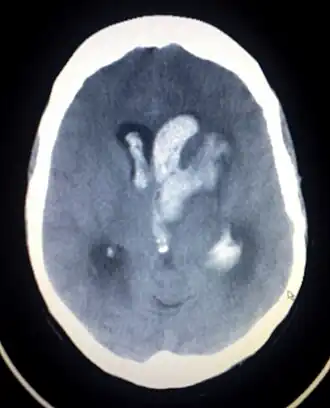

A hemorragia intraparenquimatosa pode ser reconhecida na tomografia computadorizada porque o sangue aparece mais brilhante do que outro tecido e é separado da mesa interna do crânio por tecido cerebral. O tecido que envolve um sangramento é muitas vezes menos denso do que o resto do cérebro por causa do edema e, portanto, aparece mais escuro na tomografia computadorizada.[14]